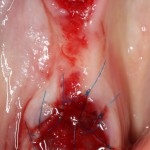

Очень аккуратно удалили зуб. Убрали из лунки все грануляции. В область верхушки корня зуба — Neocones, остальная часть альвеолы — Bioss Collagen. Сама лунка запечатывается Mucograft Seal:

Который подшивается к ее краям:

Пациенту даются обычные рекомендации после удаления зуба. Контрольный осмотр — через день: